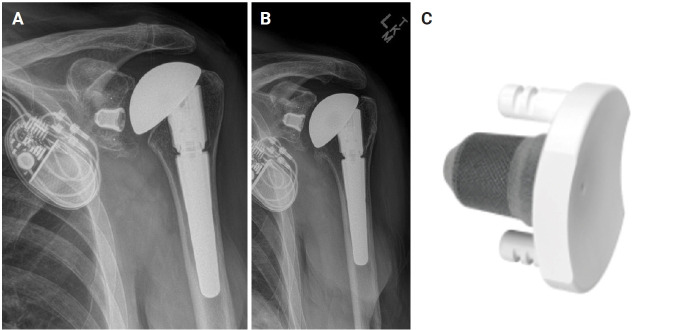

Abstract Image